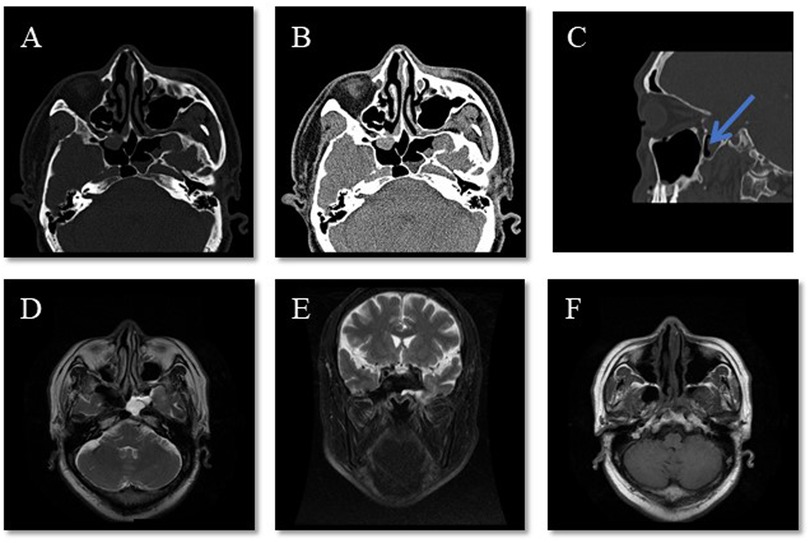

An otherwise healthy 60-year-old man presented to the Otolaryngology Department with a 6-month history of clear watery discharge from the left nostril following trauma. He denied any symptoms at the time of impact, but developed intermittent non-mucoid rhinorrhea from the left nostril 2 weeks later. Upon admission, the general physical examination, including the patient’s respiratory, cardiovascular, abdominal, and neurological systems, was unremarkable. The nasal examination revealed a normal appearance, and endoscopic nasopharyngoscopy showed watery discharge from his left nasal cavity without mucosal edema, congestion, or other symptoms (Figure 1A). An analysis of the nasal discharge revealed elevated glucose levels (6.78 mmol/L) and chlorine levels (183.7 mmol/L), suggesting it was CSF. Radiological investigations, including computed tomography of the patient’s sinuses (Figures 2A–C) and magnetic resonance imaging of his sinuses and brain (Figures 2D–F) showed a continuous disruption in the lateral wall of the left sphenoid sinus, leading to CSF leakage, and a suspicion of herniated brain tissue in the left sphenoid sinus, namely meningoencephalocele. The patient was preoperatively diagnosed with traumatic sphenoid sinus meningoencephalocele with CSF rhinorrhea.

Figure 2

Six-panel medical image with labeled sections A to F. Panels A and B are axial CT scans of the skull, showing different tissue densities. Panel C is a sagittal view CT scan with an arrow indicating a specific area of interest. Panels D, E, and F are MRI scans, with D and F showing axial views and E showing a coronal view, highlighting various brain structures.

Figure 2. Representative radiographical images upon admission. (AC) CT of the patient’s sinuses shows a continuity disruption in the lateral wall of the left sphenoid sinus and meningoencephalocele in the sinuses. The arrow indicates direct apposition between the sphenoid sinus recess and the posterior maxillary wall without intervening vascular structures. (DF) MRI of the sinuses and brain shows effusion in the left sphenoid sinus and an abnormal cystic signal, which raised suspicion of it being brain tissue.